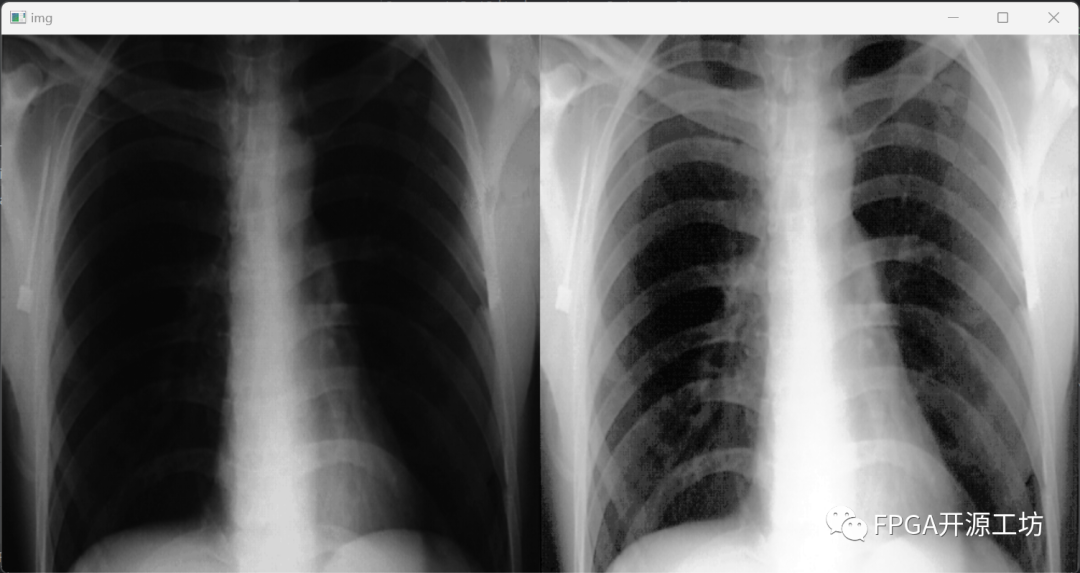

如下图就是经过直方图均衡化后的效果图。

左边是原图,右边是经过直方图均衡化后图,可以看到肋骨什么的可以更加清晰的显示了出来,能够更好的观察到肋骨等位置的细节。

但是美中不足的是总感觉有的地方太亮了,干扰到了我们的观察。